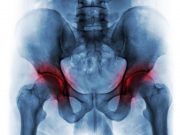

Racial Differences Seen for Joint Replacement Care and Outcomes

Differences seen across the continuum of care for knee, hip total joint arthroplasty for osteoarthritis